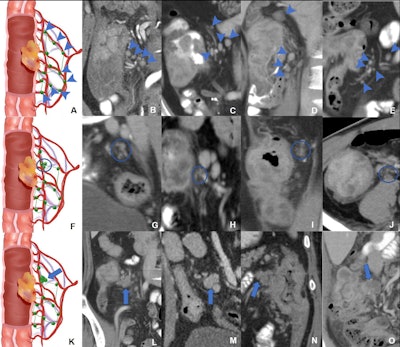

Schematic diagrams and representative images of different distribution patterns of region lymph nodes detected at CT. (A) Vascular distribution pattern: All regional lymph nodes detected at CT have regular borders and are distributed along the vessels (arrowheads). (B-E) Coronal CT images in a (B) 34-year-old woman, (C) 51-year-old man, (D) 37-year-old man, and (E) 40-year-old man with microsatellite instability-high (MSI-H) colon cancer show multiple clear lymph nodes distributed along the supplying arteries or draining veins (arrowheads). (F) Jammed cluster pattern: At least three lymph nodes with blurred margins and clustered (circle). (G-I) Coronal CT images in a (G) 29-year-old man, (H) 35-year-old man, and (I) 67-year-old man and (J) axial CT image in a 43-year-old man with MSI-H colon cancer show several lymph nodes with blurred margins and clustered (circle). Movies 1-4 provide more details. (K) Fused pattern: Several poorly defined lymph nodes clustered and fused together (arrow). (L-O) Coronal CT images in a (L) 63-year-old woman, (M) 59-year-old man, (N) 49-year-old woman, and (O) 73-year-old man with MSI-H colon cancers show several lymph nodes fused (arrow). Image courtesy of Radiology.Schematic diagrams and representative images of different distribution patterns of region lymph nodes detected at CT. (A) Vascular distribution pattern: All regional lymph nodes detected at CT have regular borders and are distributed along the vessels (arrowheads). (B-E) Coronal CT images in a (B) 34-year-old woman, (C) 51-year-old man, (D) 37-year-old man, and (E) 40-year-old man with microsatellite instability-high (MSI-H) colon cancer show multiple clear lymph nodes distributed along the supplying arteries or draining veins (arrowheads). (F) Jammed cluster pattern: At least three lymph nodes with blurred margins and clustered (circle). (G-I) Coronal CT images in a (G) 29-year-old man, (H) 35-year-old man, and (I) 67-year-old man and (J) axial CT image in a 43-year-old man with MSI-H colon cancer show several lymph nodes with blurred margins and clustered (circle). Movies 1-4 provide more details. (K) Fused pattern: Several poorly defined lymph nodes clustered and fused together (arrow). (L-O) Coronal CT images in a (L) 63-year-old woman, (M) 59-year-old man, (N) 49-year-old woman, and (O) 73-year-old man with MSI-H colon cancers show several lymph nodes fused (arrow). Image courtesy of Radiology.